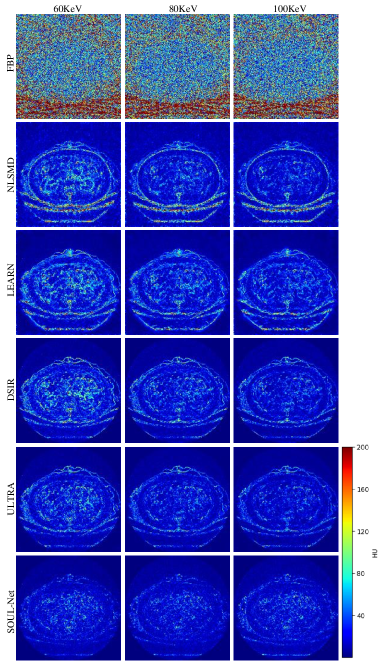

To better verify the detail recovery ability, Fig. 3 shows the absolute difference images associated with the reference image. In Fig. 3, it is clear that SOUL-Net has the smallest residual compared with other methods. This indicates that our method is able to preserve the structural details effectively.

The NPS of all results are shown in Fig. 4. We can see that in both high- and low-frequency bands, the error in the results of SOUL-Net is lower than that of the other methods. This can be treated as additional evidence of the effectiveness of our proposed method.